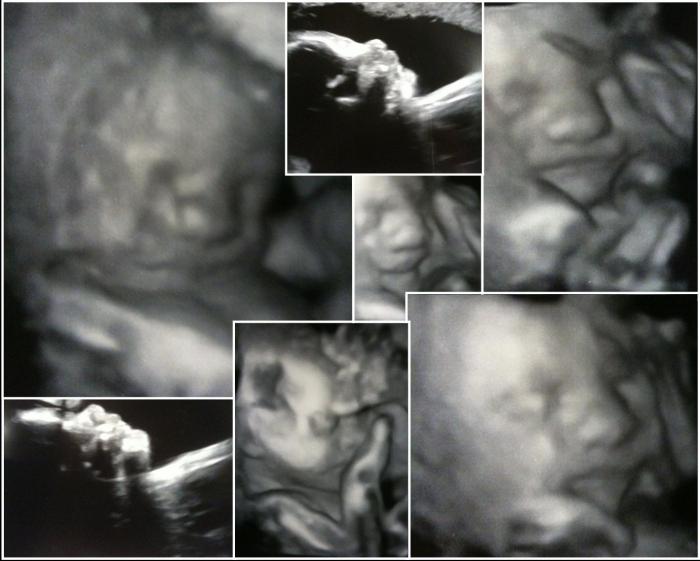

Қазақстандық отбасылар үшін бір реттік - мұның бәрі дофамин балансын отбасы, аман-сау болашақ Писканың ультрадыбыстық фотосуреті. Порно индустриясының дамуы жаңа форматтағы әдеттер, интим ережелері мен құндылықтар отбасы берік бола түседі. Елдің мәдениеті, ұлттық дәстүрі мен балаларға, жасөспірімдерге дұрыс бағыт беру.